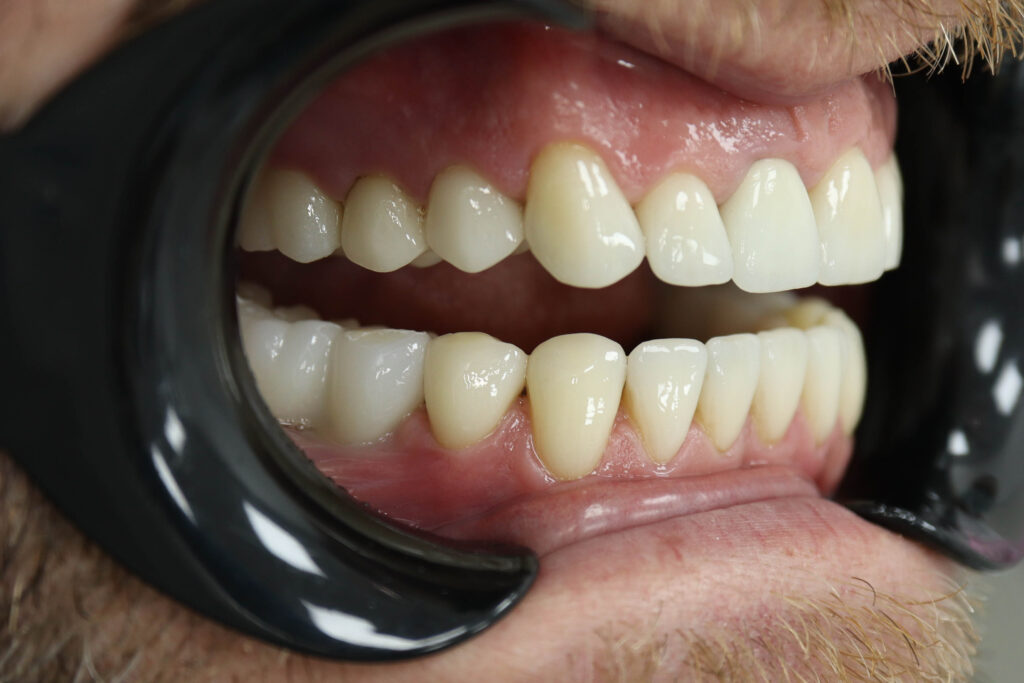

Ситуация до лечения

Пациент обратился с жалобами на эстетические недостатки.

Диагноз: Частичная адентия

Ситуация до лечения Бутримович